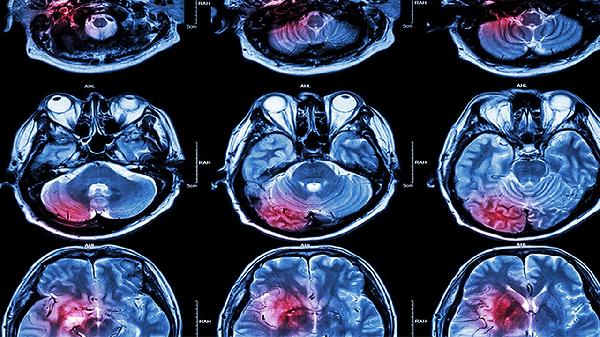

脑供血不足需要补血吗 找出原因才是治脑供血不足关键

脑供血不足通常不需要补血,关键需查明病因。脑供血不足可能由动脉粥样硬化、颈椎病变、心脏泵血功能异常、血液黏稠度增高、血管痉挛等因素引起,治疗需针对具体病因采取改善循环、控制基础疾病等措施。